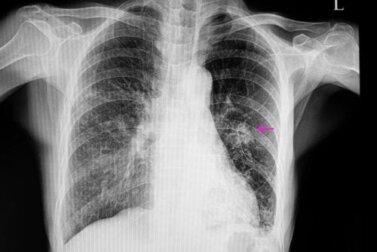

Completata la storia clinica, è necessario eseguire alcuni test di imaging per individuare il nodulo. Le immagini consentono anche di osservare alcune caratteristiche, come la forma e le dimensioni, che sono importanti per differenziare una condizione benigna da una potenzialmente maligna.

Quelli usati più spesso sono la radiografia del torace e la tomografia computerizzata o TAC. Per conoscere esattamente la causa scatenante del nodulo polmonare, a volte vengono eseguite delle biopsie che consentono di analizzare il tessuto che lo forma.

In questi casi, di solito i noduli appaiono irregolari dalla radiografia, con bordi scarsamente definiti. Generalmente sono anche più piccoli di quelli benigni e sono associati ad alcuni fattori di rischio, come: